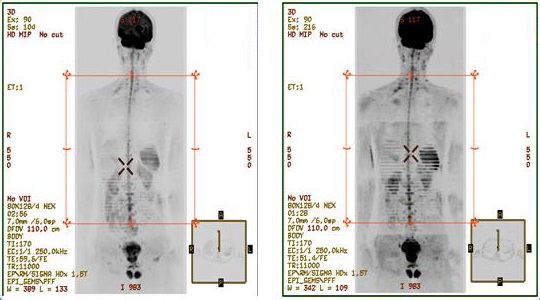

Figure 1. Comparison of epi2alt and default DWI images

Table 1. Image legend

NumberDescription

1Images acquired with DWI pulse and type-in: epi2alt

2Images acquired with the default DWI pulse.